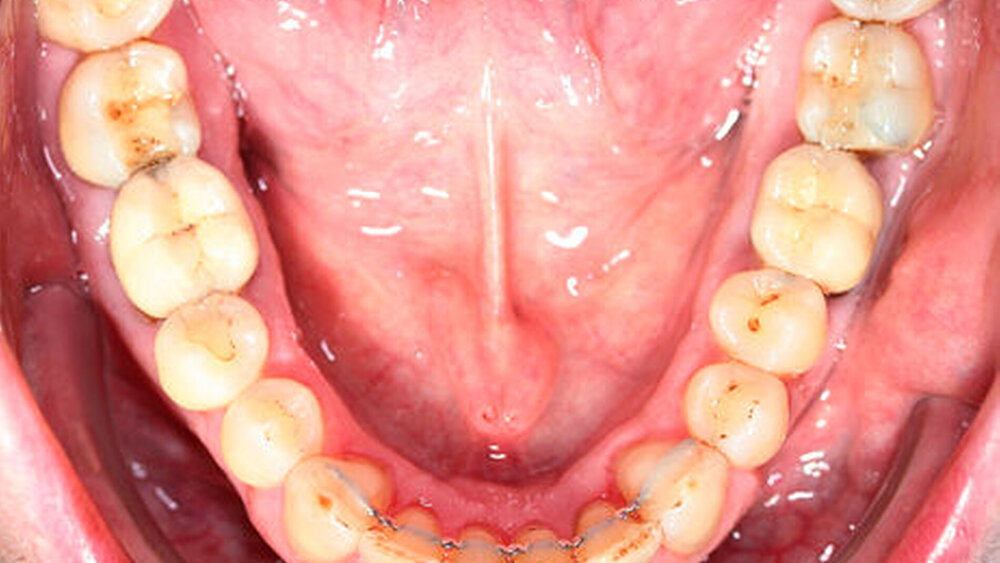

Die Sulkustiefen konnten auf etwas weniger als 4 mm reduziert werden, während der Blutungs- und Plaque-Index bei weniger als 15 Prozent lag. Daher wurde eine kieferorthopädische Behandlung über die nächsten zwei Jahre in Kombination mit engen zahnärztlichen Kontrollen geplant. Als Mittel der Wahl entschieden wir uns gemeinsam mit dem Patienten für das Invisalign-System, da hiermit sowohl eine Schienung als auch eine kraft-arme Bewegung der Zähne möglich sein sollte. Für den Frontzahnbereich wurden keine Attachments geplant, so dass hier eine unnötige Hebelwirkung umgangen werden konnte (Abbildung 3).

Um einen kompletten Lückenschluss im Oberkiefer zu ermöglichen, musste im Unterkieferfrontzahnbereich zusätzlich zur Derotation und Positionierung der Zähne – insbesondere Zahn 41 – von approximaler Schmelzreduktion, kurz ASR , Gebrauch gemacht werden, um einer Tonn`schen Diskrepanz entgegenzuwirken (siehe dazu Abbildung 7 auf Seite xy).

Nach Ausgliederung der insgesamt 14 Invisalignschienen, die der Patient jeweils drei Wochen getragen hatte, wurden ihm sowohl im Unter- als auch im Oberkiefer Sechs-Punkt-Retainer eingegliedert, um eine Schienung und Stabilisierung der Zähne untereinander zu ermöglichen.